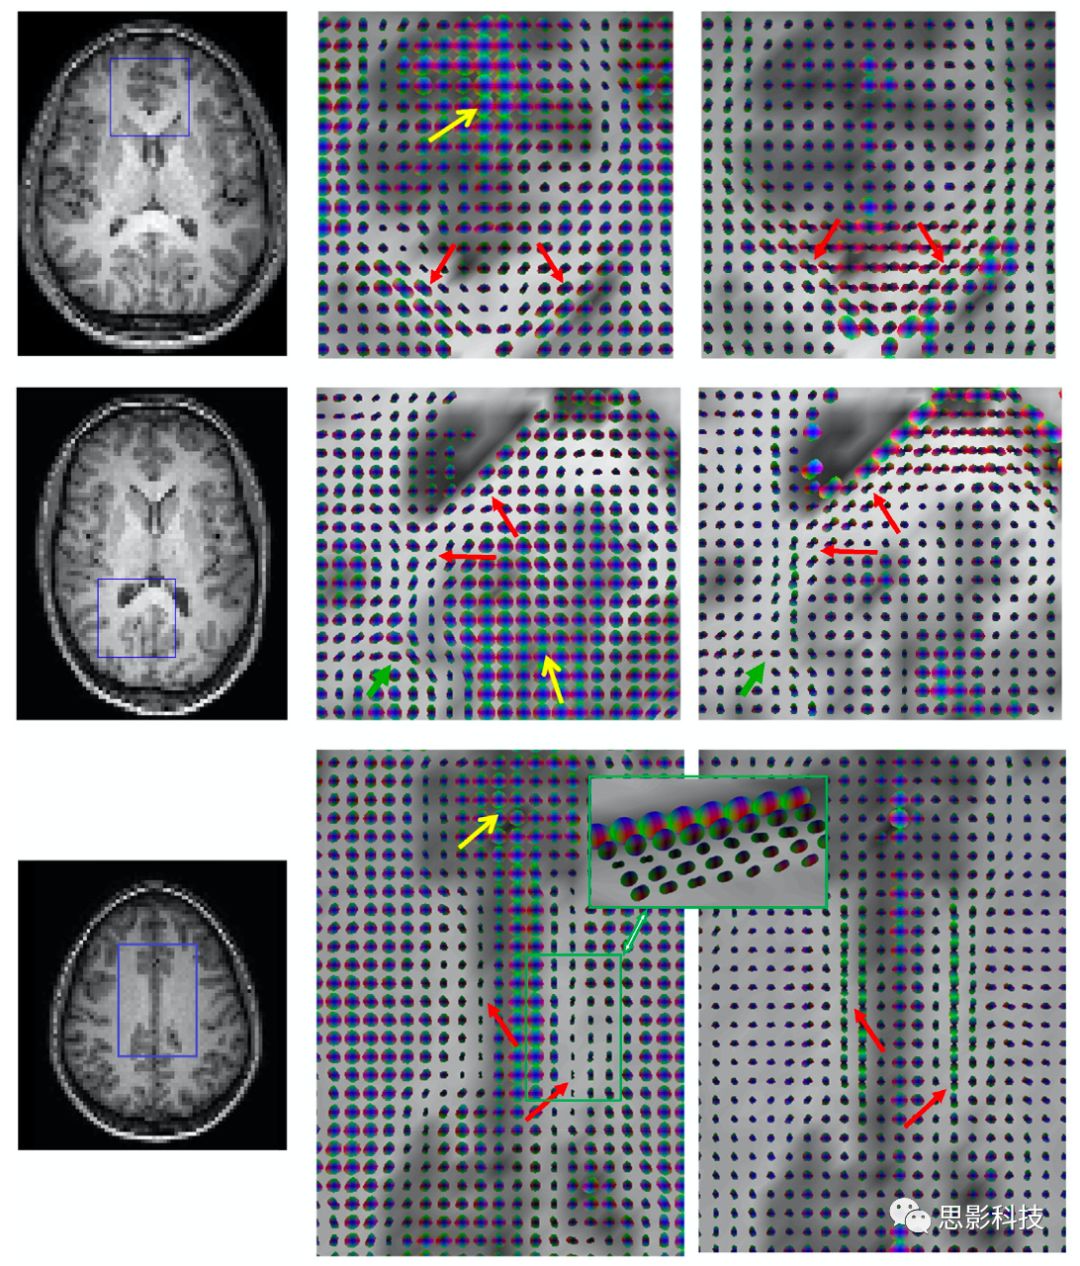

Ding等人還計算了相鄰WM體素之間信號的相關性,發(fā)現(xiàn)它們是具有可測量的各向異性特征。對于3×3×3體積中心的體素,有26個最近的鄰居,因此在靜止狀態(tài)下有26個方向的相關系數(shù)。WM中的這些值是不相等的,但它們可能適合當做是3×3張量,就如DTI中不同的梯度方向。靜息態(tài)下BOLD信號的函數(shù)相關張量(FCT)可用類似于DTI張量的方式處理。例如,使用它們的主特征值定義主方向,而類似的各向異性分數(shù)(FA)就很容易得到。Wang等人觀察到,感覺運動系統(tǒng)中沿WM纖維束的靜息態(tài)相關性的平均FA與卒中患者的臨床評分顯著相關。而Chen等人將FCT擴展為動態(tài)FCTdFCT)。其衍生出來的定量指標,即動態(tài)FA,被證明是可有效的識別輕度認知障礙(MCI)。一般來說,FCT定義的纖維束遵循DTI定義的纖維束。5顯示了單個腦切片的DTIFCT之間的比較比較結果,而圖6顯示了胼胝體和扣帶回中的單個體素的定向橢球體。

5. 第一行是在沒有任何擴散加權的情況下獲得的,只使用了在四個不同TEs的靜息態(tài)波動-泛函相關張量中的相關性。下面一行顯示了由M0R2*圖像、擴散張量和FA映射構造的功能相關張量。

Fig 6  胼胝體的膝部和壓部以及扣帶回中的時間功能相關性張量(FCT)和擴散張量。左圖為T1,左列的方框區(qū)域中的FCT和同一區(qū)域中的擴散張量。 FCT形成的通路與擴散張量(紅色箭頭)顯示的通路基本一致。